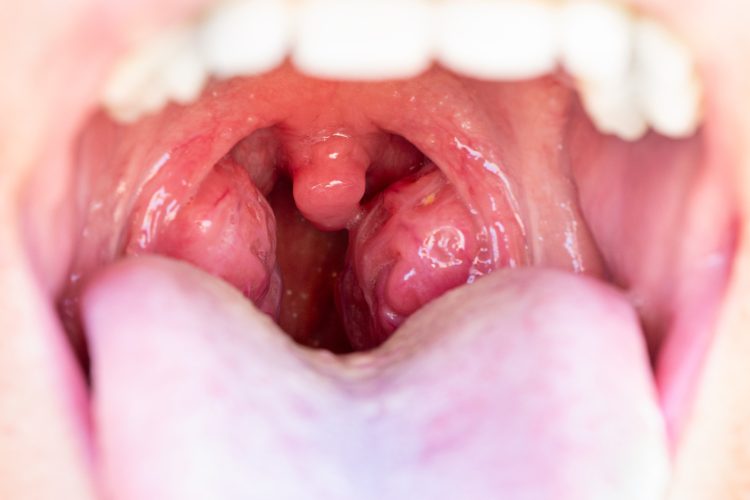

Penyebab radang amandel bervariasi, mulai dari infeksi virus (misalnya flu) hingga bakteri (seperti Streptococcus). Gejalanya bisa berupa nyeri menelan, demam, batuk, sakit kepala, dan pembengkakan amandel. Jika radang ini sering kambuh lebih dari lima kali setahun atau tidak membaik meski diobati, perlu evaluasi lebih lanjut.

Radang amandel biasanya dapat diatasi dengan obat, istirahat, dan banyak minum. Namun, bila infeksi terus berulang atau memicu komplikasi seperti abses peritonsil, dokter bisa menyarankan operasi tonsilektomi.